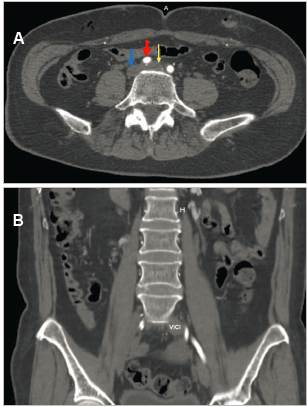

The abdominal CT showed an enlarged left common iliac vein extending toward the ipsilateral iliofemoral vein. The apparent reduction of the common iliac vein's lumen below the RCIA was notable, indicating a mural thrombus extending toward the confluence of the iliac veins at the inferior vena cava, ending in thrombosis of the iliac vein and left iliofemoral vein, with suspected May-Thurner syndrome (MTS) (Figures 3a and 3b).

Figure 3 A (Top): left common iliac vein compression (yellow arrow) by the right common iliac artery (red arrow), causing venous dilation (16 mm), with mural thrombi inside. Inferior vena cava (blue arrow). B (Bottom): coronal abdominal-pelvic section showing left common iliac vein (LCIV) thrombosis with an increased diameter compared to the contralateral vein.